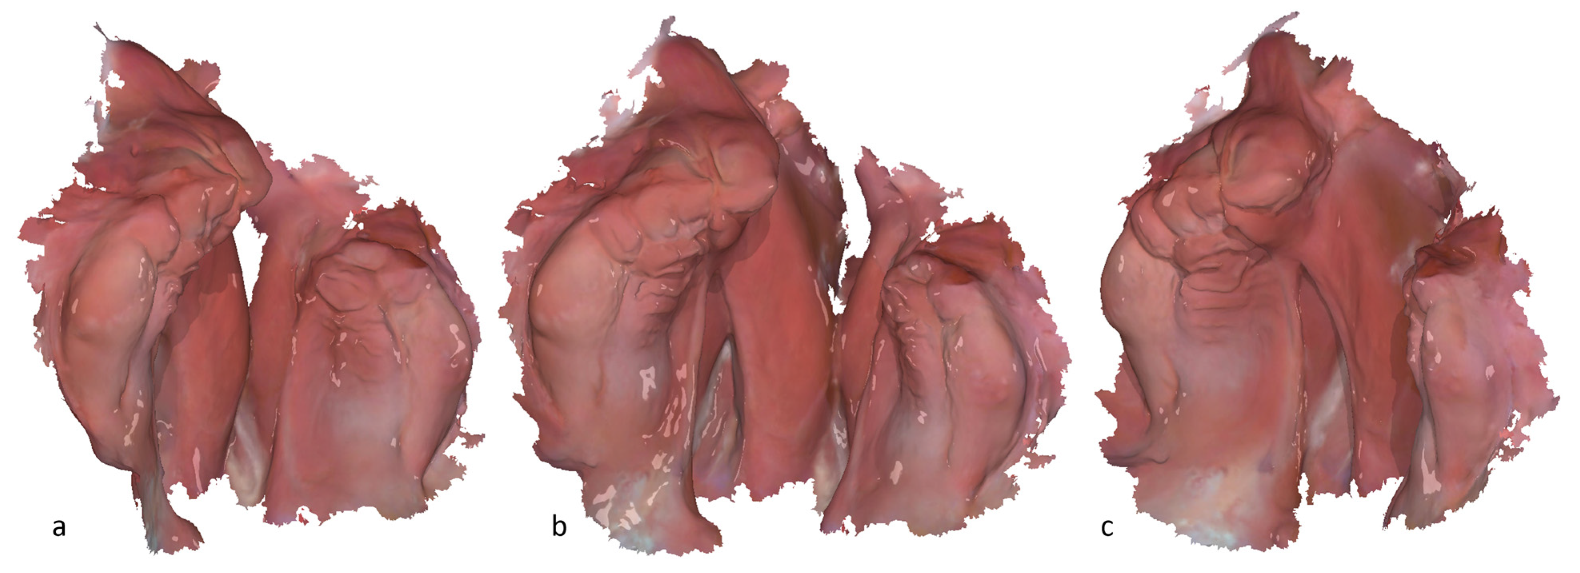

Figure 2. Intraoral 3D scan of a left-sided cleft lip, jaw, and palate: (a) tilted view with the focus on the smaller segment; (b) occlusal view of the small and large segment; (c) tilted view with the focus on the large segment.

The digital workflow of the Frankfurt approach (Figure 1, Step 1) initiates with an IOS, which serves as the foundation for subsequent digital measurement. IOS of the upper jaw segments is obtained using a 3Shape intraoral 3D scanner; both the Trios 3 and Trios 4 are in application (3Shape A/S, Copenhagen, Denmark). To ensure precise image acquisition and optimal texture quality, the intraoral 3D scanner undergoes weekly calibration per the manufacturer’s instructions. Before the initial 3D scan, the patient data are entered into the 3D scanner system. For the 3D-scanning procedure, the newborns are positioned supine on a pillow covered with a sterile pad. In order to achieve the best possible 3D scan quality, the patient’s jaw area is first cleaned superficially with the aid of a moistened gauze swab, and any adhesive cream residue is removed. Where possible, the jaw segments are then dried with the aid of dry gauze and a saliva ejector. The newborns remain awake and are not sedated during the IOS. A sterilized standard 3D scan tip of the corresponding 3Shape intraoral 3D scanner is used for the intraoral 3D scan, which typically takes about 3 min (Figure 1 and Figure 2). The IOS must be verified to ensure that all relevant anatomical features have been captured for subsequent measurement. Any missing or poorly captured areas of the alveolar ridge must be re-3D-scanned. Once the intraoral 3D scan is complete, a post-processing step is performed using the IOS software to generate an exportable 3D data set.